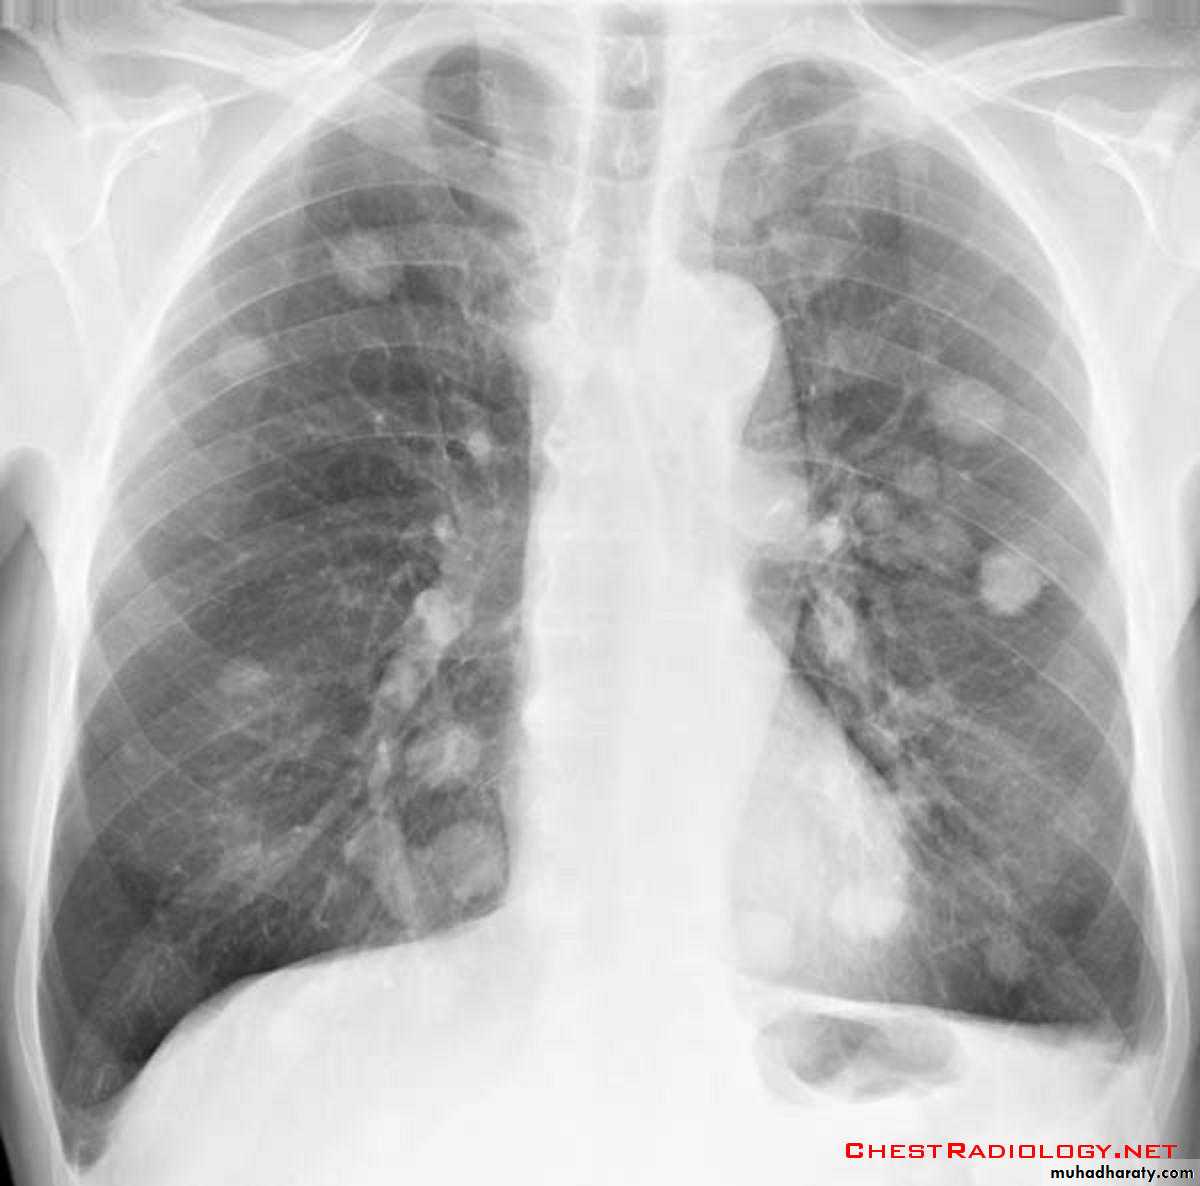

Secondary metastasis

DDX of coin shadow

74.secondary metastasis to the lung ( canon ball appearance )

75.DDX of coin shadow